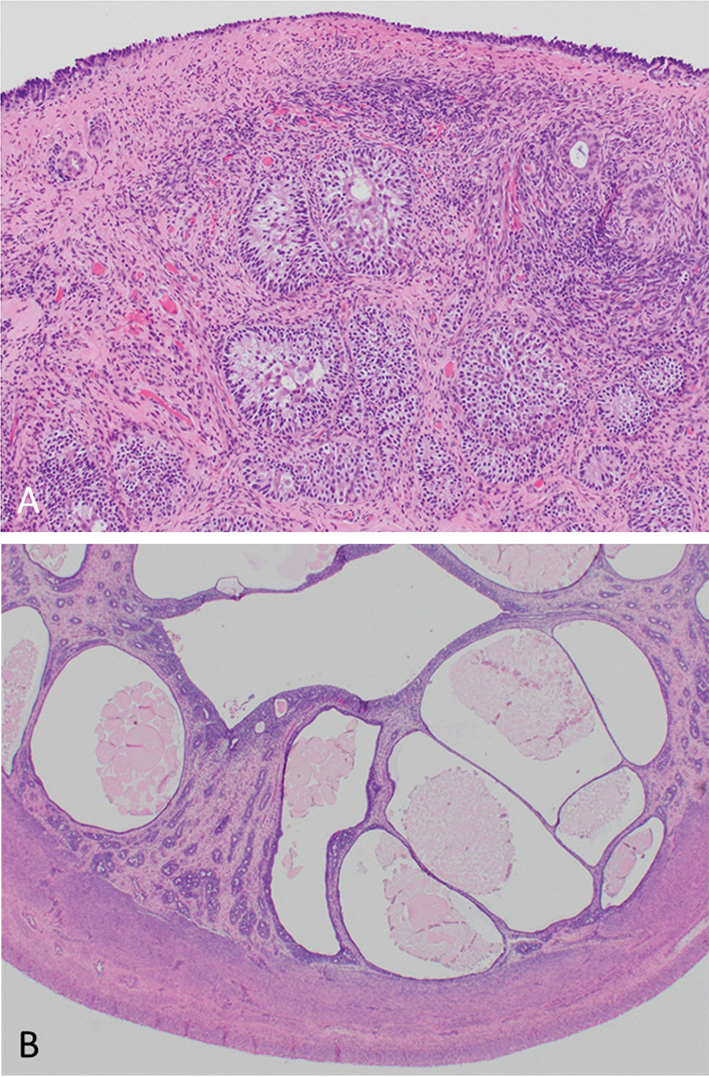

Ovariohysterectomy was performed and hormone analysis was not repeated. Gonads and surrounding tissues did not have overt cystic lesions (Figure 3). Histopathology of gonads was consistent with bilateral ovotestes with central area with a solid sheet of interstitial cells that was multifocally interrupted by scattered seminiferous tubules lined by Sertoli cells, and occasional primary spermatogonia noted in the left gonad (Figure 4A). Surrounding the seminiferous tubules, small spindle cells were present, consistent with thecal cells, and the gonads were covered by simple cuboidal epithelium. No follicles or ova were observed in either gonad. Left ovotestis was surrounded by a tubular structure, most consistent with an oviduct. Right ovotestis was surrounded by several tubules lined by columnar epithelium supported by a moderately cellular fibrovascular stroma, most consistent with epididymis. Uterus contained diffuse cystic endometrial hyperplasia with moderate to markedly dilated endometrial glands (Figure 4B). Karyotyping (Texas A&M Molecular Cytogenetics Laboratory) had a total of 77 chromosomes characterized by a single X chromosome consistent with X chromosomal monosomy (77, XO). Concurrent PCR testing for the sex determining region Y (SRY) gene was negative (Figure 5).

Figure 4.

Figure 4. Light microscopic images of reproductive tract stained with hematoxylin and eosin; scattered seminiferous tubules within stroma of left ovotestis (A [10 x magnification]) and diffuse endometrial hyperplasia and glandular dilation (B [20 x magnification]).